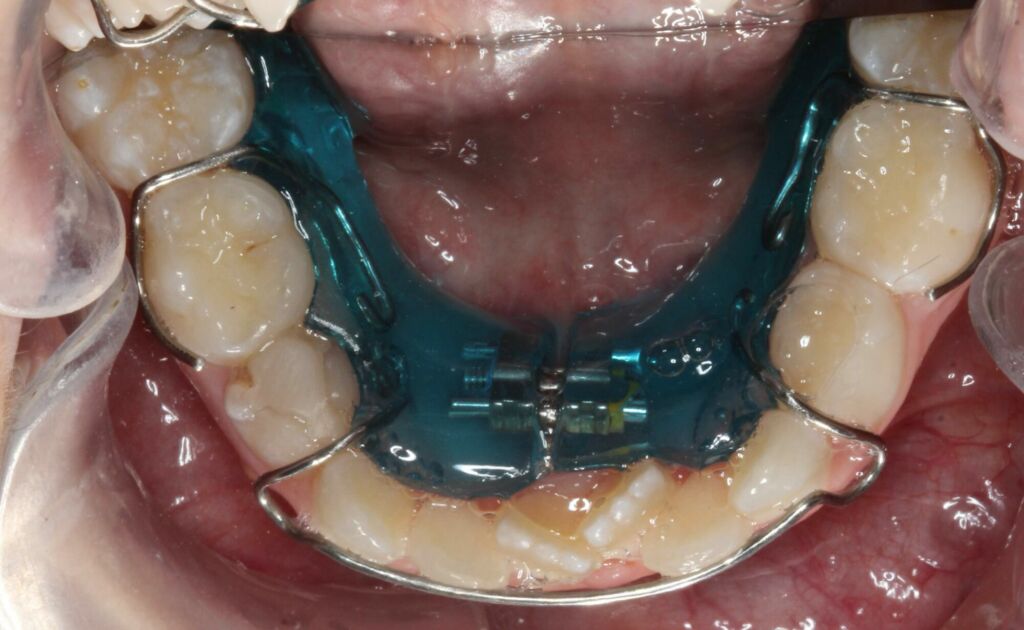

A placa de Schwarz inferior trata-se de um expansor removível utilizado para expansão lenta do arco inferior. O objetivo da placa de Schwarz é verticalizar os dentes posteriores, assim como a obtenção de espaço no arco. Este dispositivo pode ser uma alternativa interessante quando associada ao expansor fixo em pacientes em dentição mista, principalmente naqueles com apinhamento moderado, entre 3 e 6 mm.

No arco inferior podemos definir que a borda Walla limita a amplitude transversal mandibular, sendo que esta pode ser identificada através da junção entre a mucosa ceratinizada e a mucosa alveolar. Observe a flecha vermelha na imagem ao lado.

Observe na imagem abaixo a borda Walla e a relação “tampa-caixa” do arco inferior e superior. Conseguiram identificar a atresia da maxila? Conseguem identificar a inclinação dos dentes inferiores para a lingual?

Na imagem ao lado conseguimos ver uma relação transversal adequada entre o arco superior e inferior, é possível ver a diferença?

Não há um consenso na literatura para o protocolo de ativação da placa de Schwarz (figura 04), porém sabemos que há um limite para essa expansão dento-alveolar. Na prática clínica utilizamos a placa por cerca de 4 a 5 meses antes da instalação do disjuntor considerando um protocolo de ativação de ¼ de volta por semana. Sendo que, durante o período de ativação a placa é utilizada durante o dia todo, removendo-a somente para comer, escovar e fazer atividades físicas.